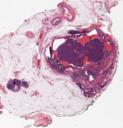

11-Mamma

Organpathologie » Gyn und Mamma » 11-Mamma

Organpathologie-Atlas